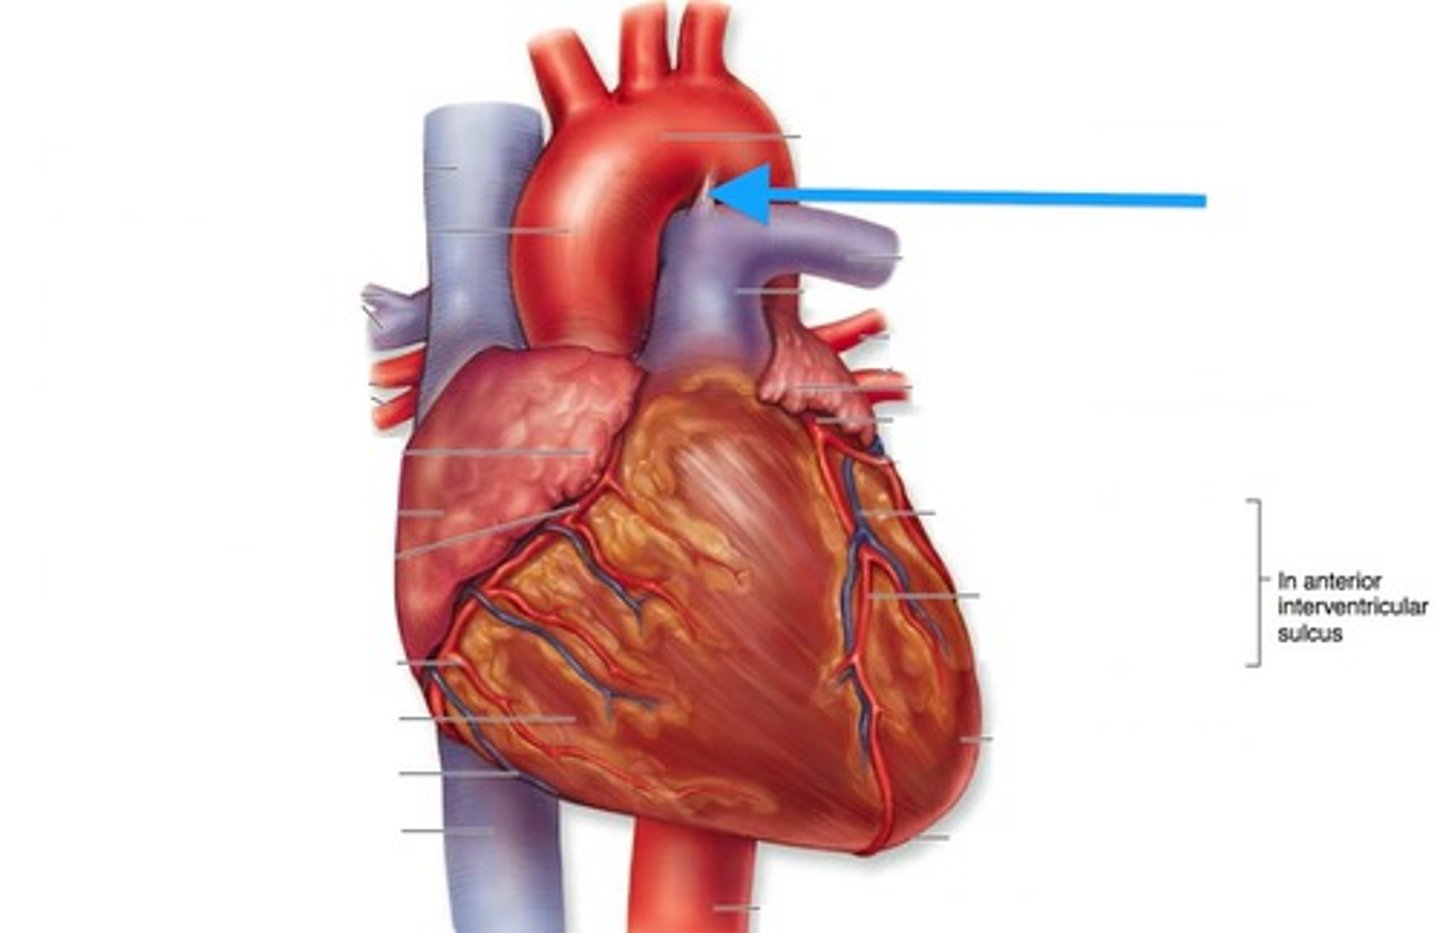

Left anterior descending artery

Structure. In the anterior interventricular sulcus.

Cardiac veins

structure. T shaped

Great cardiac vein

structure.